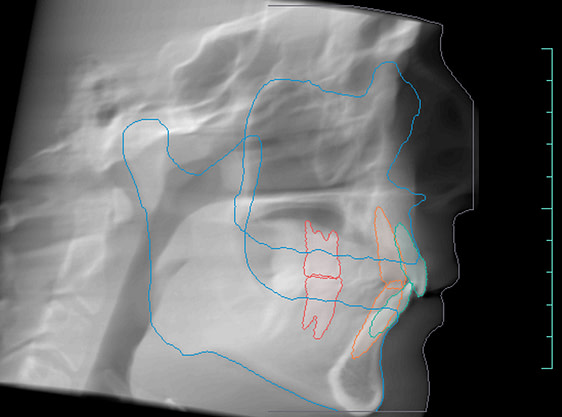

Orthodontic Report

Diagnocat is also capable of generating orthodontic reports.

This requires a CBCT radiograph with a minimum field of view of 13 x 15 x 15cm. Our Kavo OP3D machine achieves this by taking a double-field exposure and stacking two exposures on top of each other.

Diagnocat generates OPG and frontal and lateral cephalometric reconstructions from the CBCT data.

Tracings of the maxilla, mandible, central incisors, canines and molars. All automatically.

Cross-sectional and coronal views of teeth show torque and buccolingual relationships such as crossbite.

TMJ coronal/sagittal slices and summations visualize abnormal positioning/shape of the mandibular condyle.

The orthodontic report generates OPG and front/lateral cephalograms. These are not as sharp as true OPG and cephalograms. Tracings of the maxilla, mandible, central incisors, canines, and molars are automatically produced on the generated frontal/lateral cephalogram.

I showed the orthodontic report to an orthodontist colleague. She found the tracings to be fairly accurate compared to a real lateral cephalogram of the same patient. She did further tracings on the generated lateral ceph and advised it was difficult to visualize points such as Nasion, ANS, A Point, Condylion, and Orbitae and visualize the fourth vertebrae to determine peak growth phase. Furthermore, other orthodontic software can automatically calculate skeletal/dental relationships, planes, and angles.